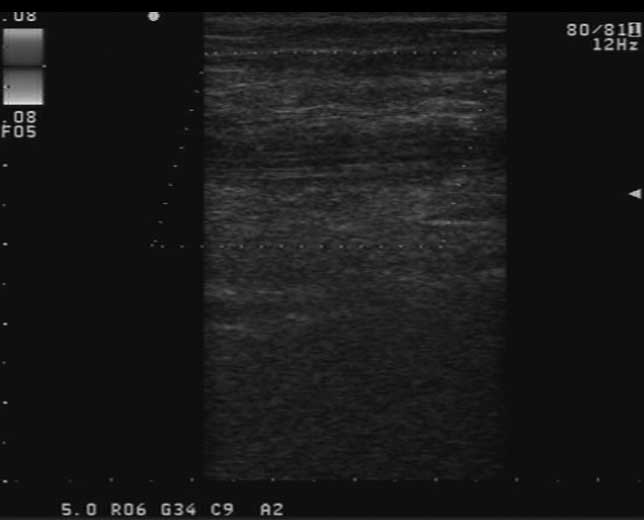

aspirin was administered. On days 10–13 of chemotherapy, Doppler

ultrasound examination confirmed a long thrombus along the PICC

line in the axillary and brachial veins in the three patients

(Fig. 1). The patients rejected